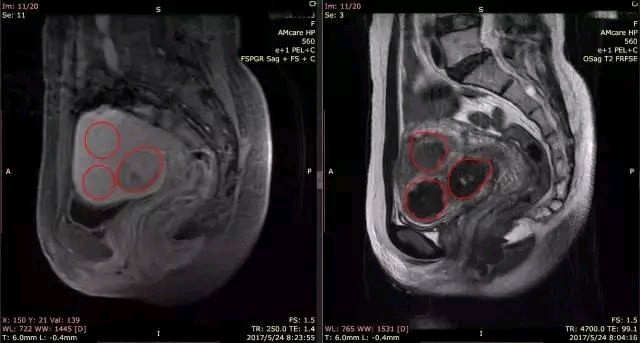

右图为T2加权平扫,3个红圈分别为3个子宫肌瘤,左图为增强后同一层面图像,其中一个肌瘤的血供低于子宫肌层,另2个肌瘤血供和子宫肌层相当